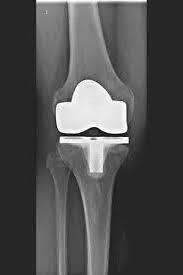

TKA (مفصل الركبة الاصطناعي)

يحل مفصل الركبة الاصطناعي محل سطح الغضروف الذي دمره التهاب المفاصل العظمي. يظل العظم الأساسي في عظم الفخذ والرأس الظنبوبي سليمًا. يقارن البعض مفصل الركبة الاصطناعي الحديث بتتويج الأسنان؛ والمصطلح الدقيق هو ما يسمى بإعادة تسطيح اللقمتين. بين الأسطح الجديدة في الجزء العلوي والسفلي من الساق يوجد ما يسمى بالبطانة المصنوعة من البلاستيك الأبيض المقوى خصيصًا، والتي يمكن رؤيتها في صورة الأشعة السينية على أنها المسافة بين الأجزاء المعدنية.